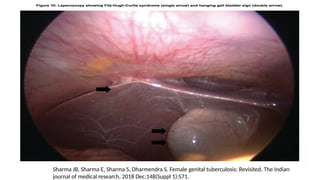

Diagnostic laproscopy

• A laparoscopy under general anaesthesia is the most reliable modality

for the detection of FGTB and abdomino-pelvic TB, particularly

affection of oviducts, ovaries and peritoneum.

• Questionable lesions maybe biopsied in an attempt to obtain

histopathological diagnosis at the same time.

• Most common findings are pelvic adhesions followed by tubal

pathology, occlusions, tubo-ovarian mass, ascites and caseous and

granulomatous nodules.

Sharma JB, Sharma E, Sharma S, Dharmendra S. Female genital tuberculosis: Revisited. The Indian

journal of medical research. 2018 Dec;148(Suppl 1):S71.